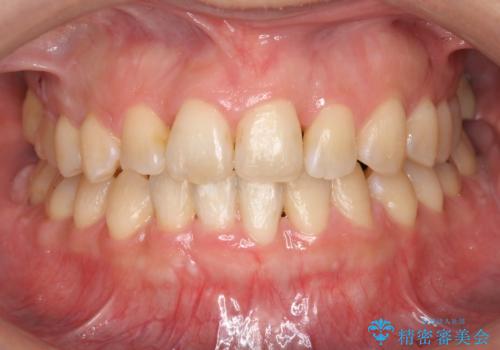

ワイヤーによる全体的ながたつきの矯正治療